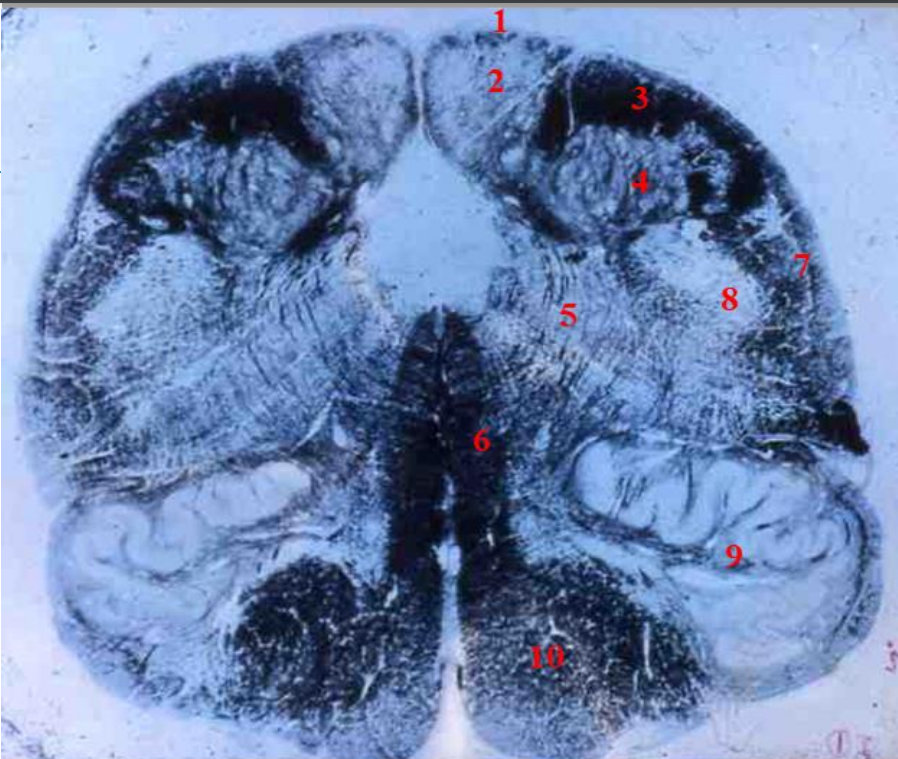

2

3

4